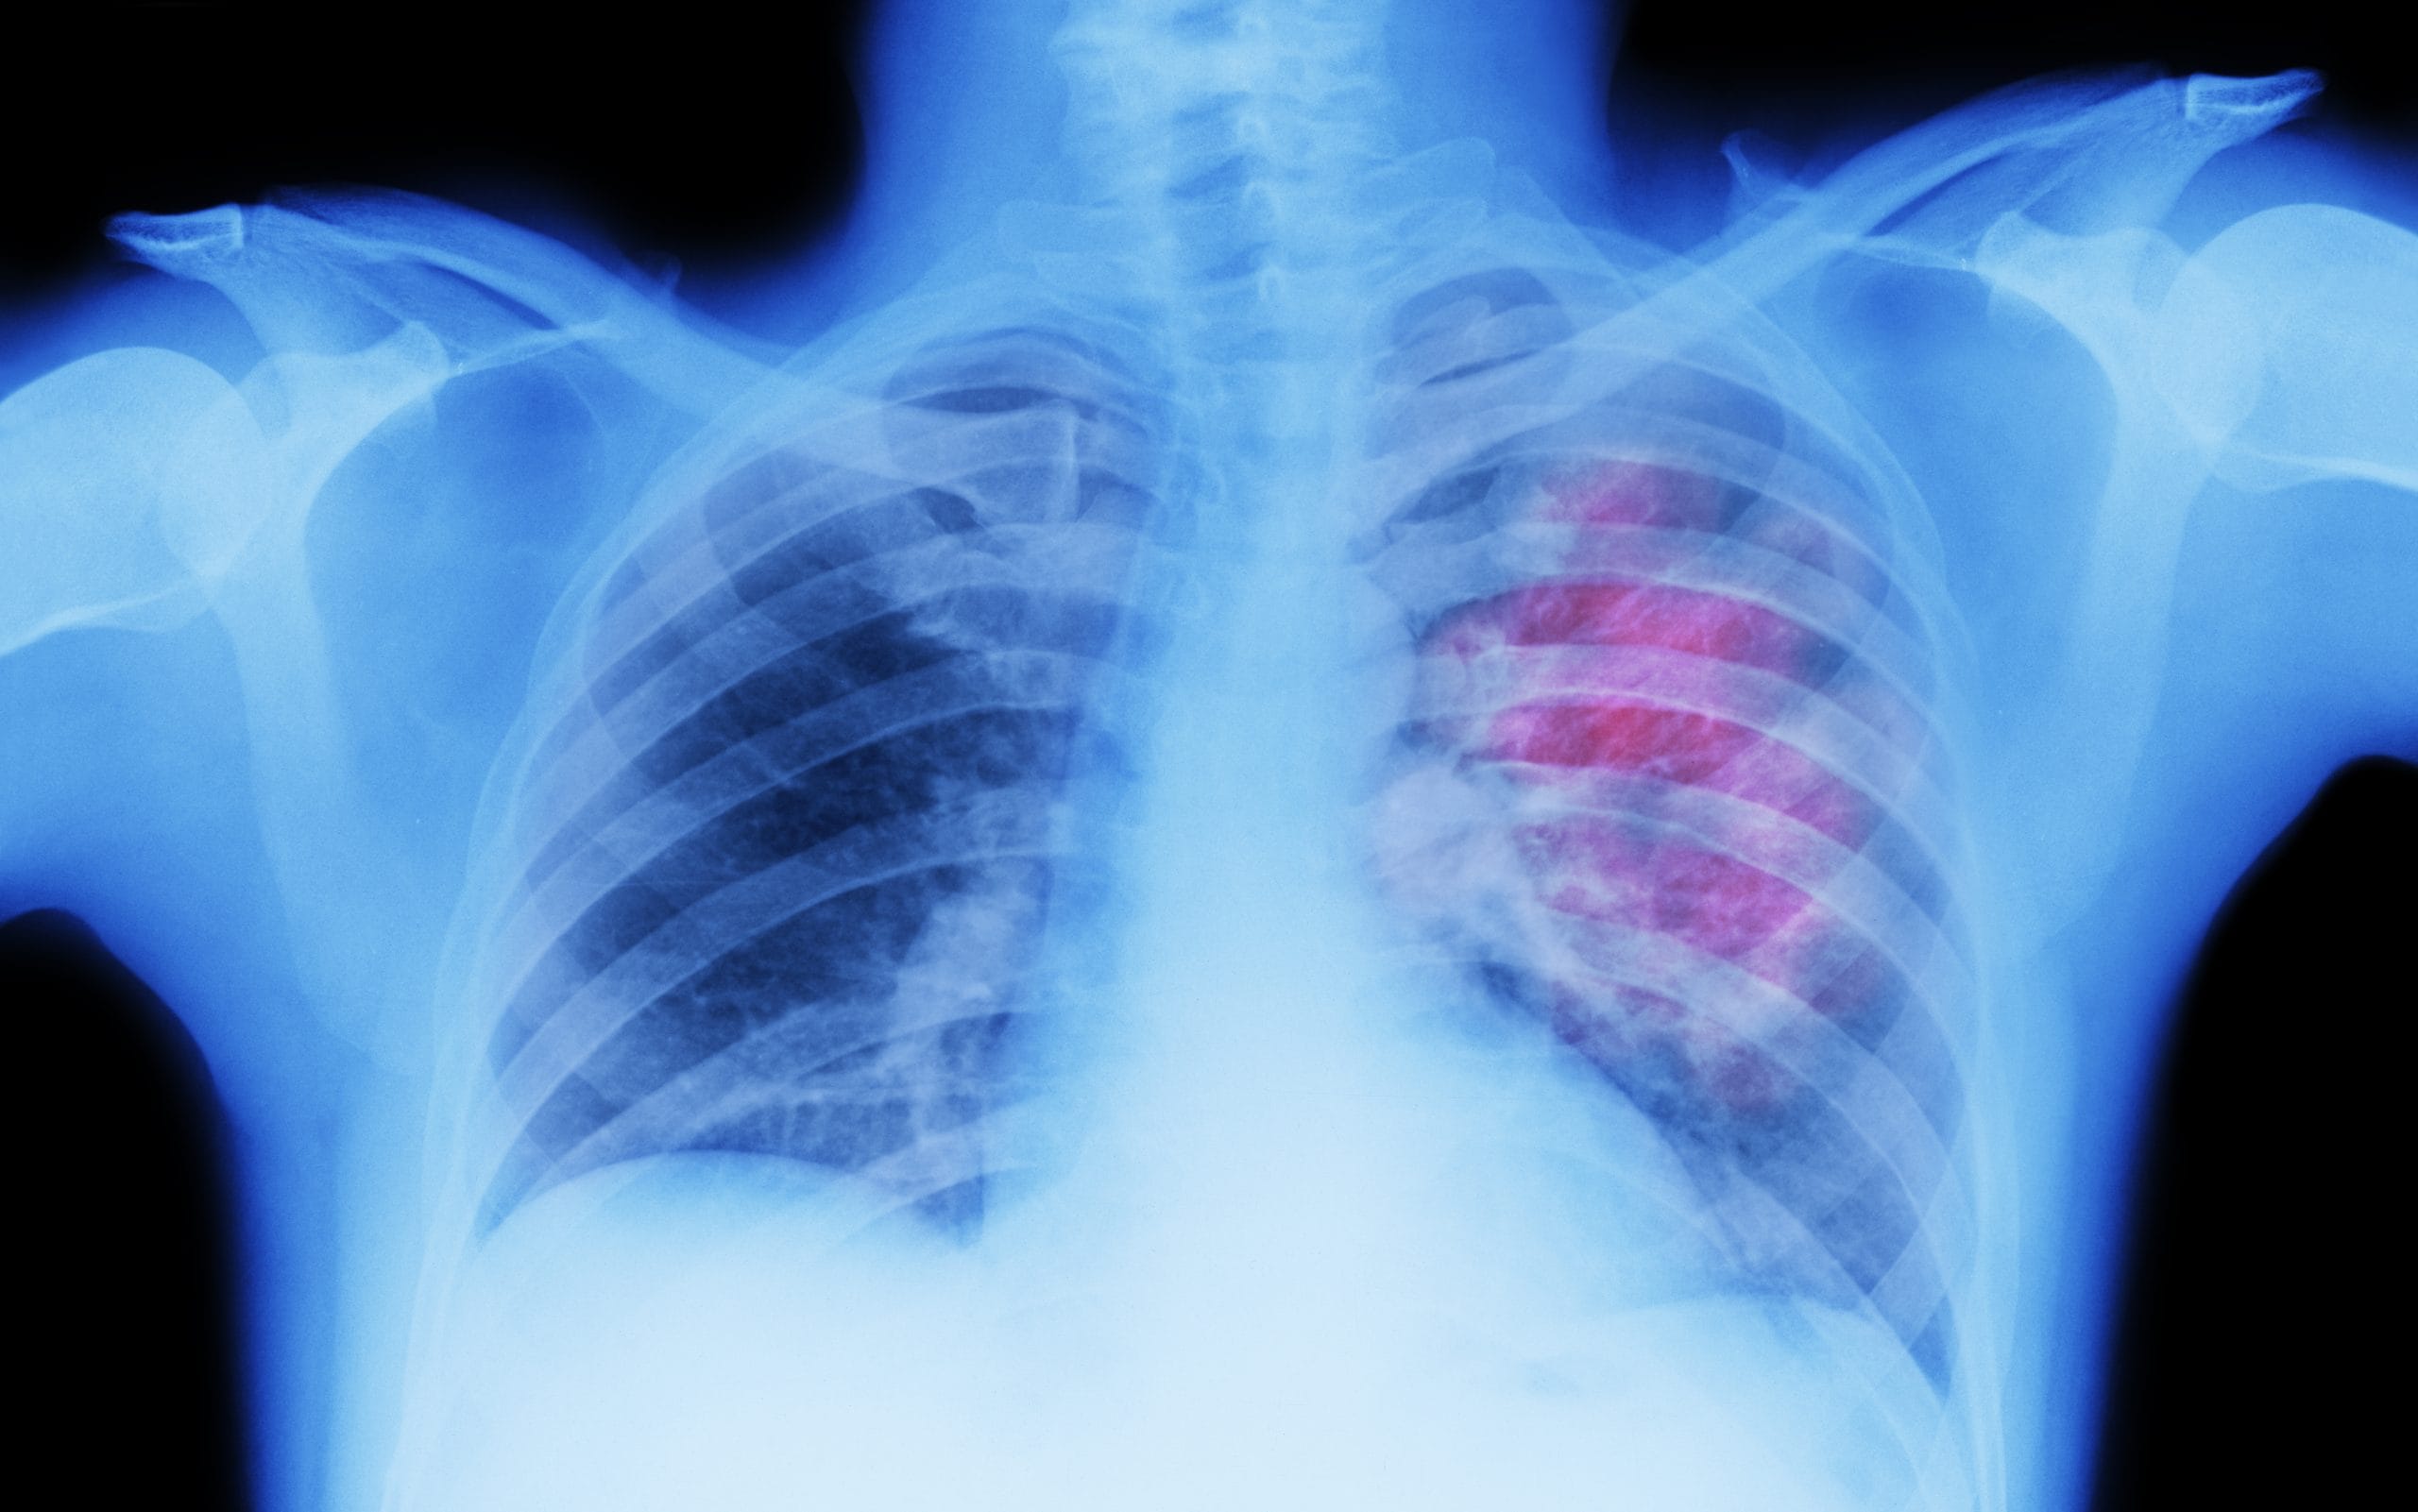

হাওঁফাওঁৰ কৰ্কট ৰোগৰ প্ৰাৰম্ভিক লক্ষণ কি ?

TV9 ASSAM

ধূমপানেই হাওঁফাওঁৰ কৰ্কট ৰোগৰ আটাইতকৈ সাধাৰণ কাৰণ, লগতে বায়ু প্ৰদূষণ। বৰ্তমান উন্নত চিকিৎসাৰ ফলত হাওঁফাওঁৰ কৰ্কট ৰোগত মৃত্যুৰ হাৰ কমিছে।

হাওঁফাওঁৰ কৰ্কট ৰোগৰ প্ৰাৰম্ভিক লক্ষণসমূহ মৃদু । এই লক্ষণবোৰ কেনেকুৱা ধৰণৰ জানি লওক।

হাওঁফাওঁৰ কৰ্কট ৰোগৰ প্ৰাৰম্ভিক লক্ষণ স্থায়ী কাহ। অবিৰতভাৱে যদি আপোনাৰ কাহ হৈ থাকে সাৱধান হওক।

উশাহ-নিশাহ লোৱাত অসুবিধা, বুকুৰ বিষ, ওজন কমি যোৱা আদি হাওঁফাওঁৰ কৰ্কট ৰোগৰ সাধাৰণ লক্ষণ।

তেজ কাহ, সঘনাই উশাহ লোৱাত কষ্ট পোৱা, হঠাতে দ্ৰুত ওজন কমি যোৱা আদি ইয়াৰ গুৰুতৰ লক্ষণ হ’ব পাৰে।

যিকোনো ব্যক্তিয়ে এই লক্ষণসমূহ অনুভৱ কৰিলে লগে লগে চিকিৎসকৰ পৰামৰ্শ ল’ব লাগে।